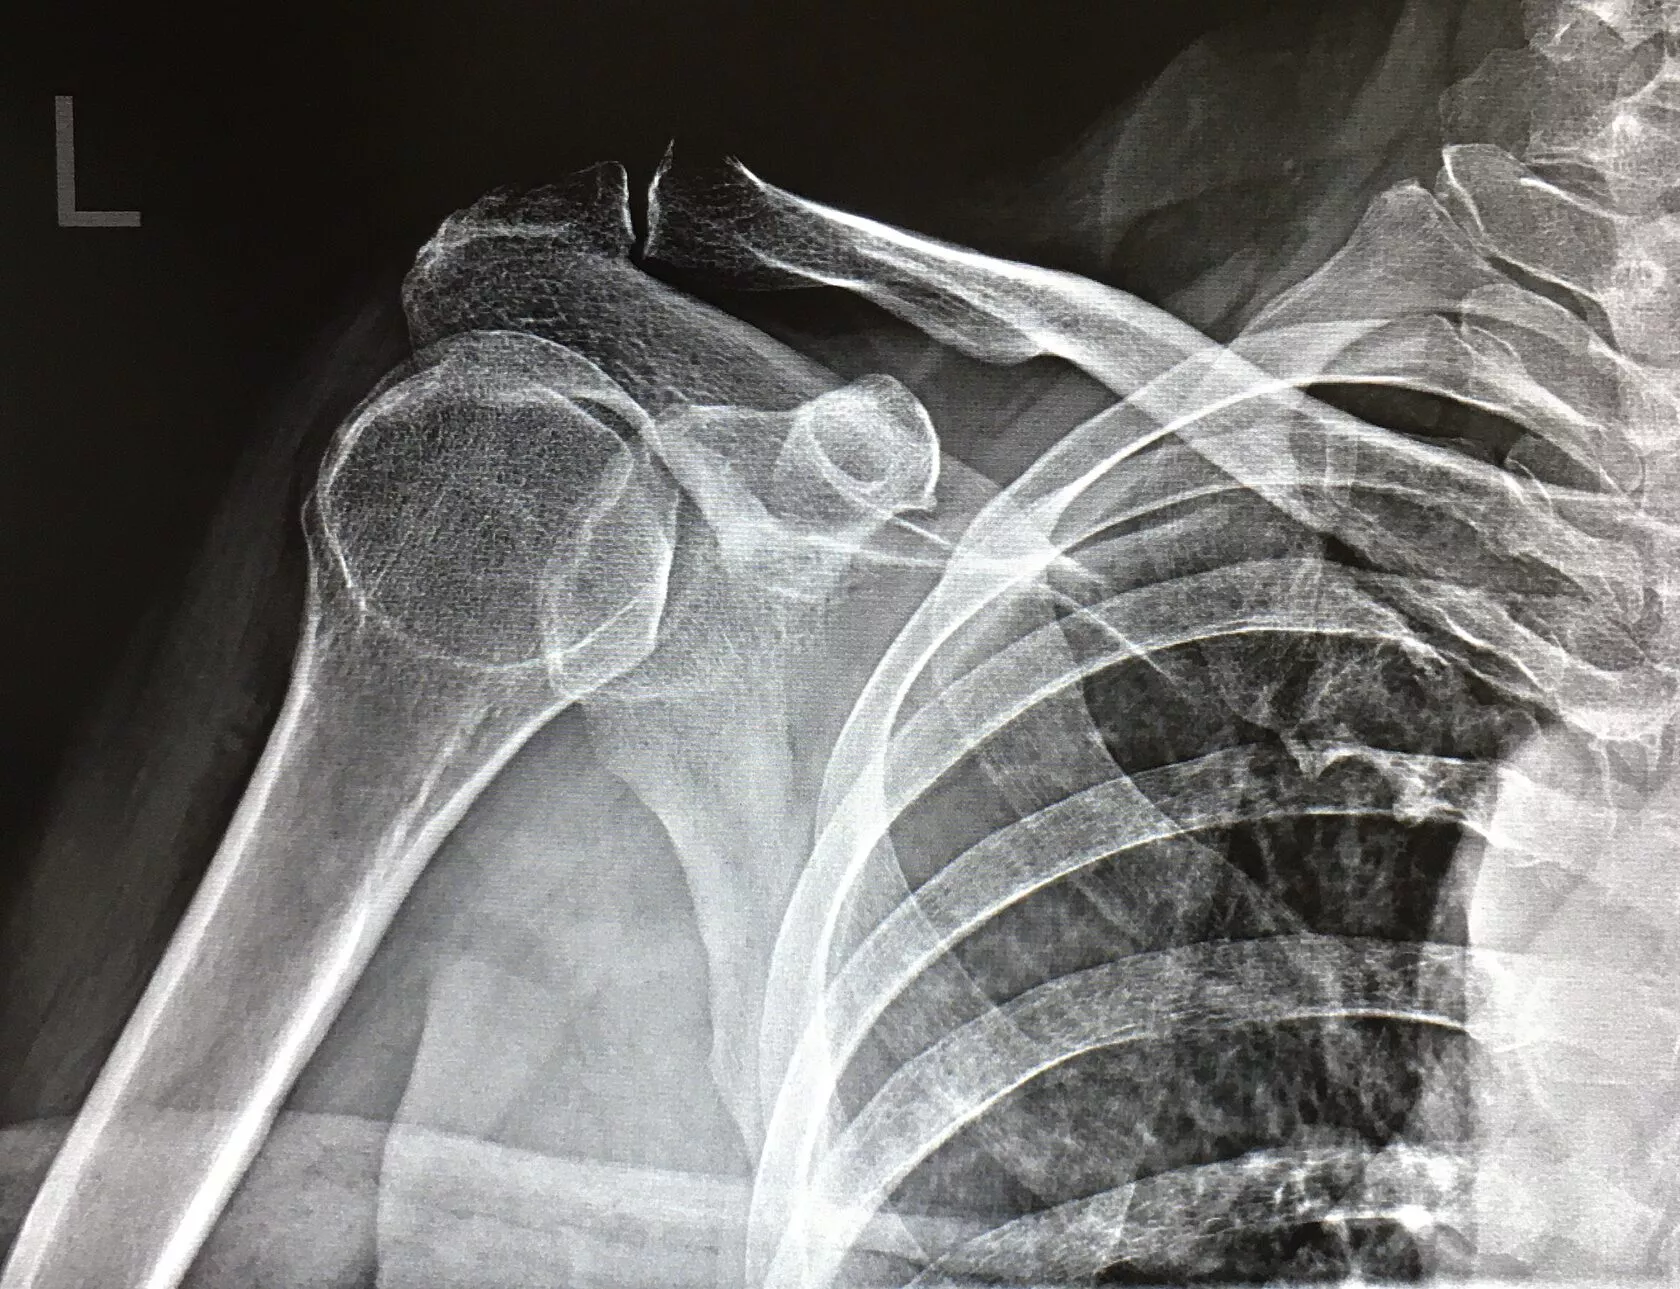

Рентген плечевого сустава

Рентген плеча позволяет оценить анатомическое строение плечевого сустава — костей и связок, выявить воспаление и новообразования, диагностировать переломы, вывихи и другие последствия травм. Также исследование назначается при диагностике артроза, артрита и остеопороза. С помощью рентгенодиагностики можно определить и вид перелома (открытый, закрытый, оскольчатый, со смещением и т.д.).